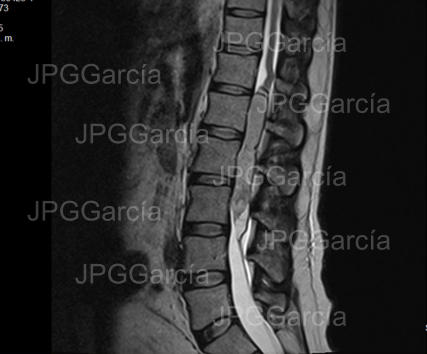

Estudio de resonancia magnética prequirúrgico que demuestra

una lesión tumoral torácica relacionada a un meningioma

RESECCIÓN MICROQUIRÚRGICA DE MENINGIOMA TORÁCICO

Estudio de resonancia magnética prequirúrgico que demuestra una lesión tumoral torácica relacionada a un meningioma